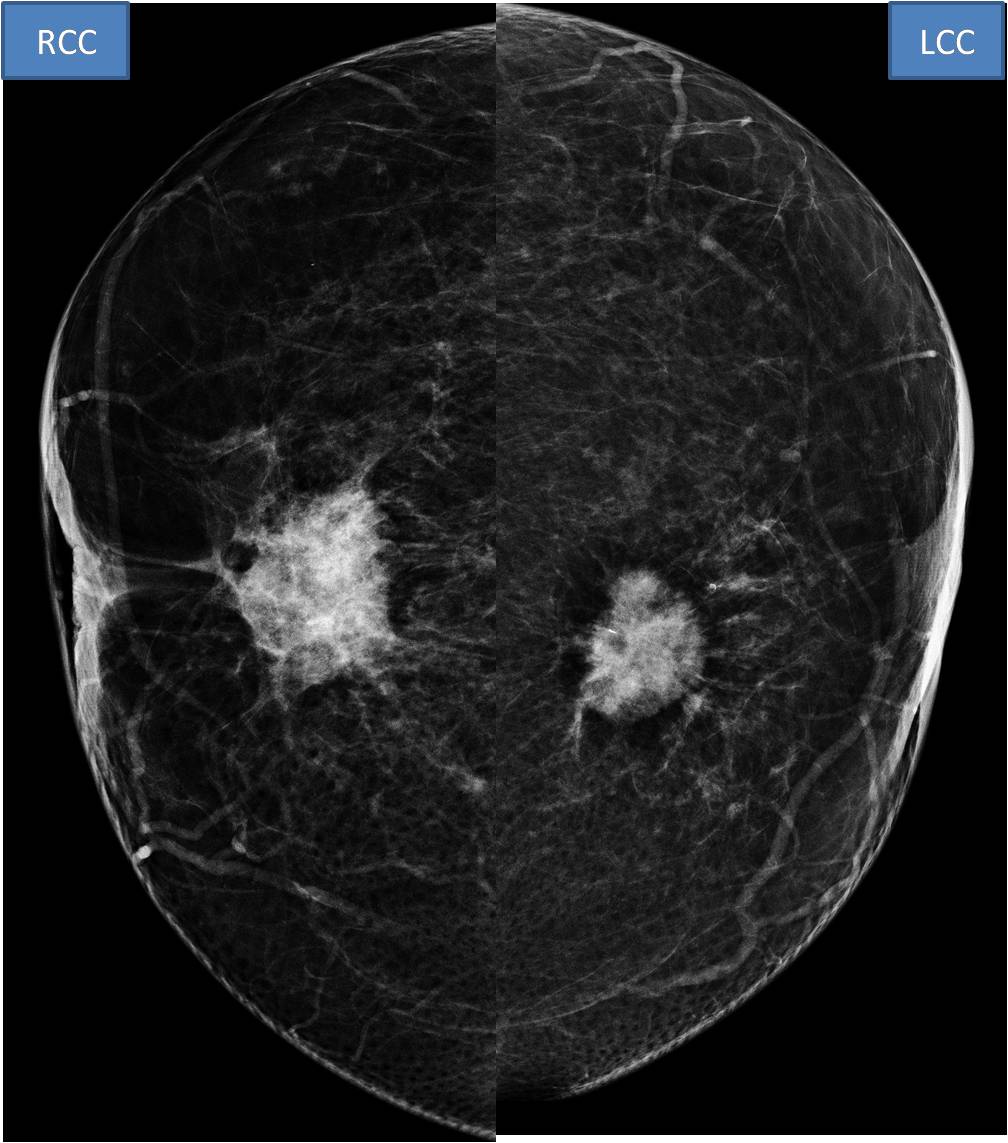

Impression: Bilateral BIRADS-5 mass. Bilateral primary breast carcinoma Next steps: - Bilateral breast mass core biopsy (confirmed IDC) - Referral to 'high risk breast clinic' as bilateral breast cancer

Mammography Right: upper central high density irregular shaped mass with spiculated margin. Nipple retracted. Left: upper central high density mass with spiculated margin. Nipple retracted. Ultrasound: findings described with images